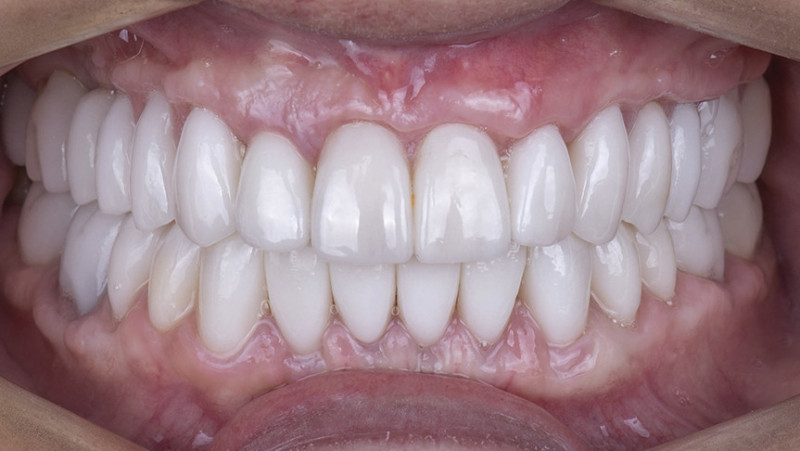

Установка керамической коронки

Изготовили и установили 22 керамические коронки EMAX и 6 виниров на нижнюю челюсть. Провели пластику десны в области 22 зуба. Устранили сильную рецессию десны в области имплантата, установленного в другой клинике.